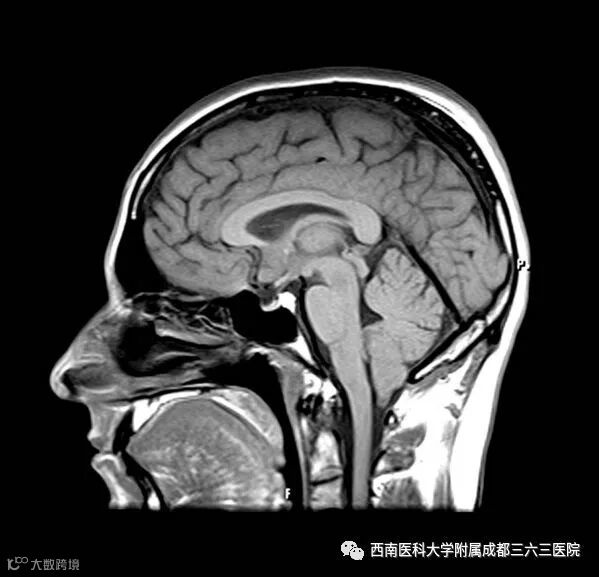

MRI, 专业称呼为核磁共振,顾名思义,它的仪器是一块大磁铁,相当于用手机摇一摇,让人体中的氢质子振动起来,再平静下来,感受一下里面的振动。其主要用于发现软组织疾病,在骨科主要用于发现椎间盘病变、脊髓病变、半月板病变、炎性病变和出血性病变等。很多的软组织只有核磁才可以更好地显示,神经、肌肉、脂肪在核磁图像上一清二楚。

没有辐射!没有辐射!没有辐射!

软组织对比分辨率高,可清楚地分辨:肌肉、肌腱、筋膜、脂肪等软组织;膝关节的半月板、交叉韧带、关节软骨;子宫的肌层,子宫内膜层;前列腺的肌肉层与腺体层;心脏的心内膜、心肌和在高信号脂肪衬托下的心外膜以及最外层的心包。

可在不改变被检查者体位的情况下从任意方向切层,全面显示被检查器官或组织的结构,无观察死角,可直接做出横断面、矢状面、冠状面和各种斜面的体层图像。

MRI的成像原理是将人体放置于一个特殊的磁场内,借此让身体中的水分震动起来,然后再利用不同组织里水分的震动差异形成影像,用以区分正常组织和患病组织,它对脑、甲状腺等实质器官和大血管及心脏等有绝佳的诊断功能。

MRI检查有较高的软组织分辨率,因而对软组织疾病、中枢神经系统疾病等有巨大的优势。

MRI的应用范围也十分广泛,因为核磁共振对软组织显像比较好,在对患者的神经系统、头、颈椎、胸椎、腰椎及四肢部位的检查上有很大的优势,所以临床医生对头颅和神经系统疾病,多选用MRI进行检查。